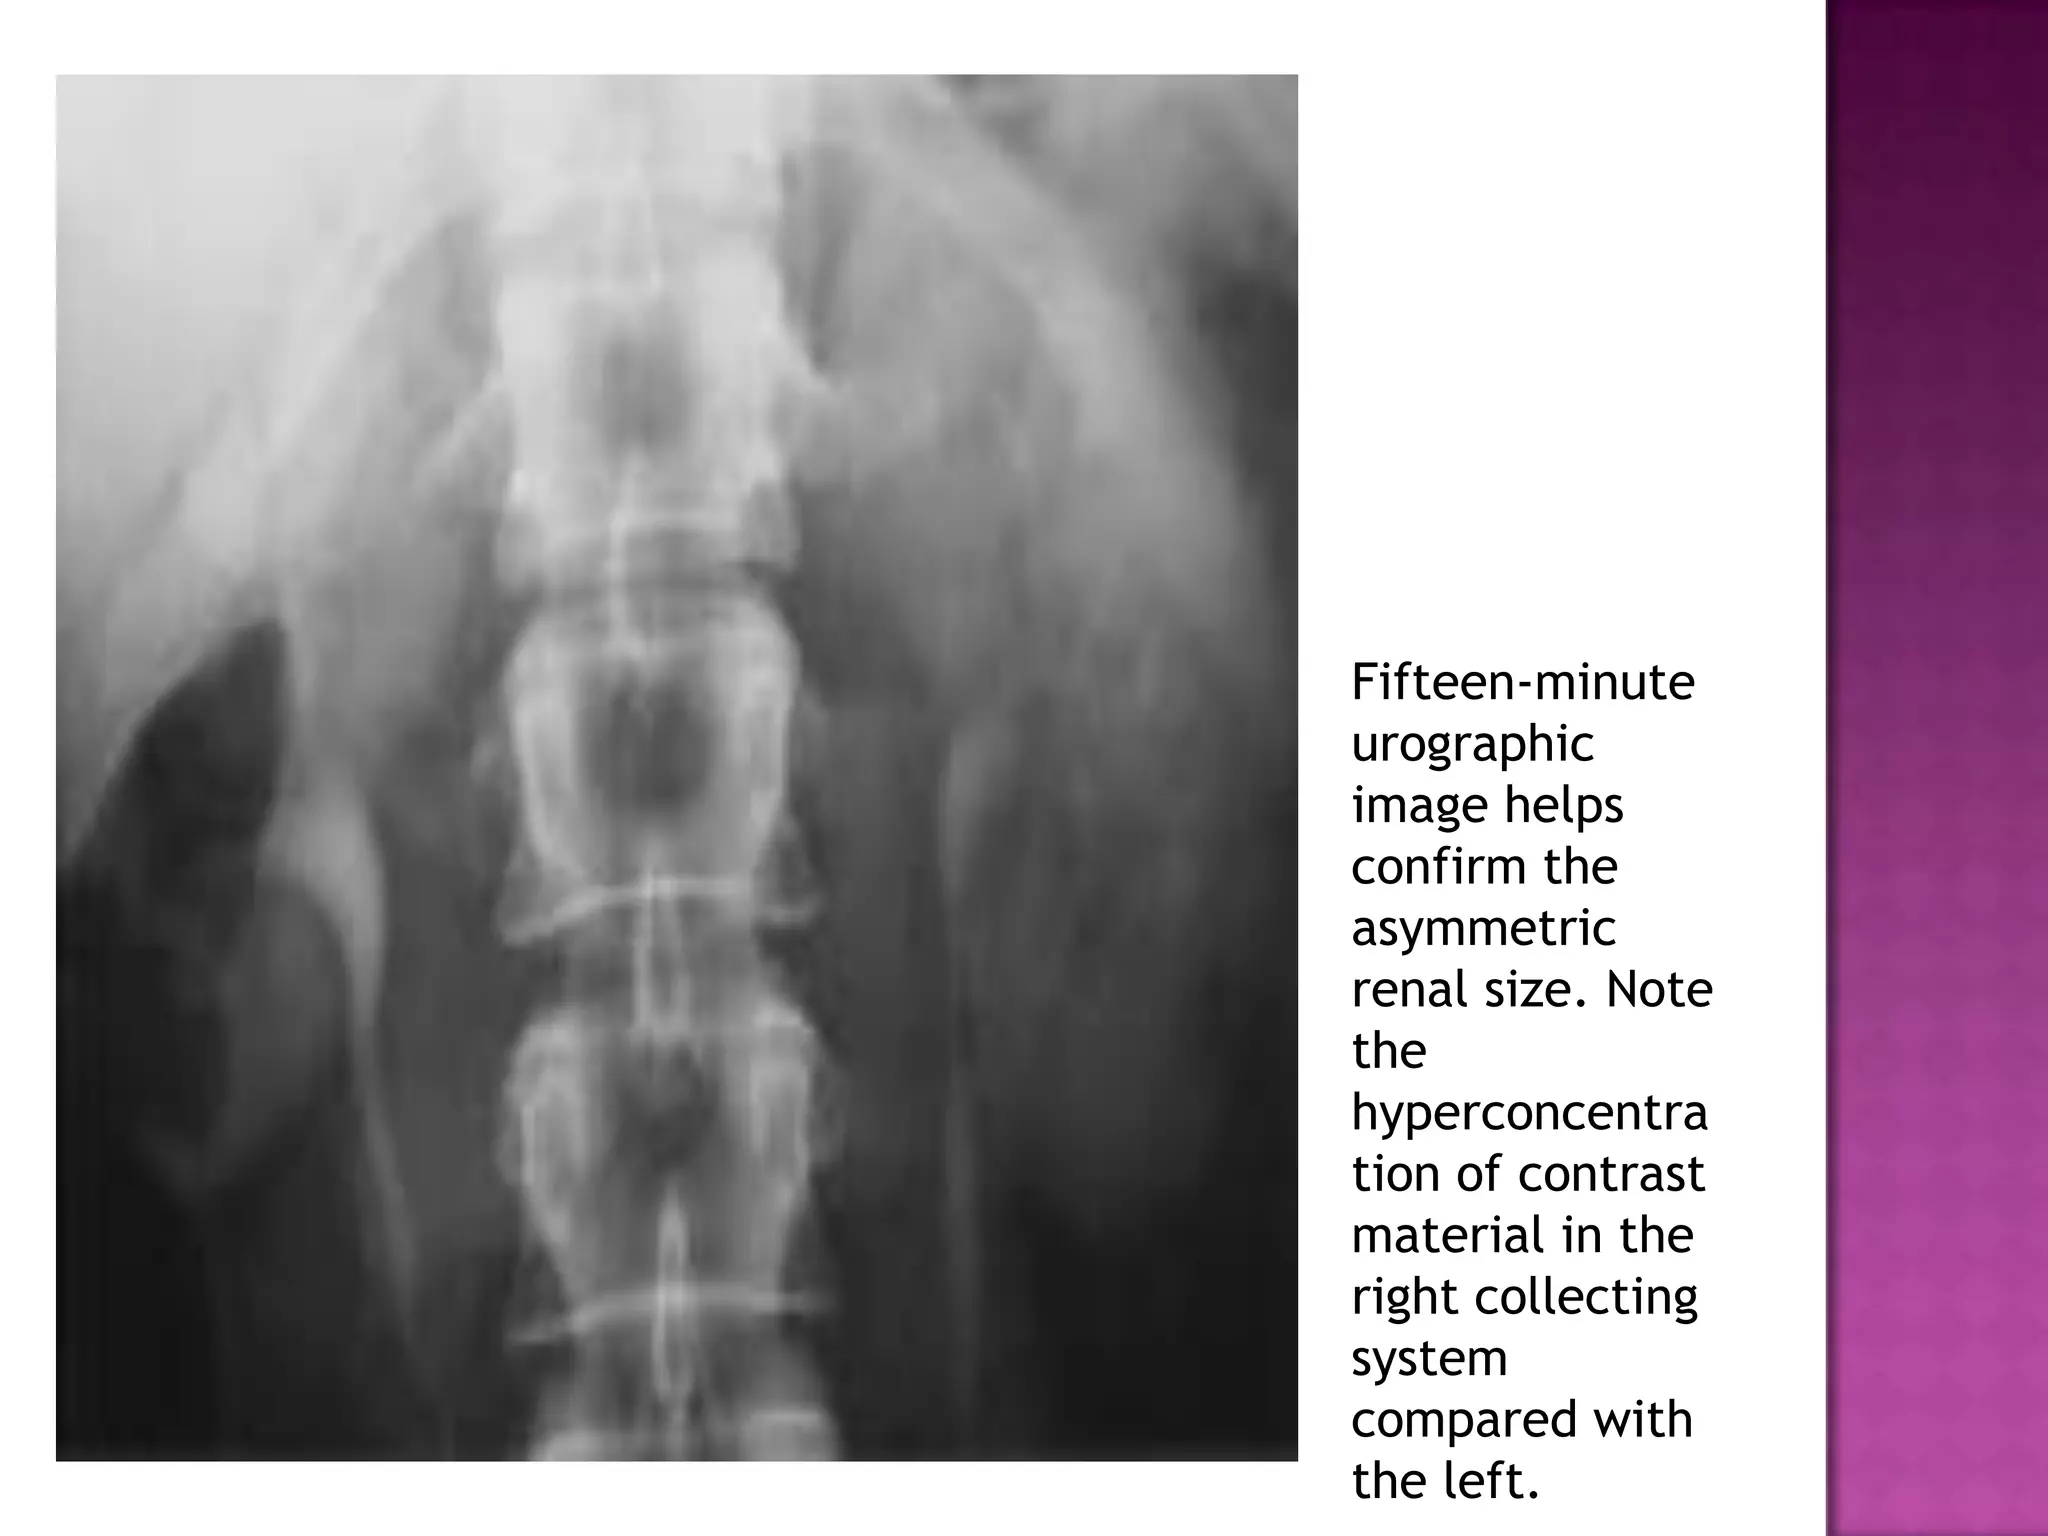

Right renal

artery

stenosis for

evaluation of

renovascular

hypertension

shows a small

right kidney

with

decreased

nephrographic

density and

temporal

asymmetry of

filling of the

right

collecting

system

compared

with the left

Fifteen-minute

urographic

image helps

confirm the

asymmetric

renal size. Note

the

hyperconcentra

tion of contrast

material in the

right collecting

compared with

the left.